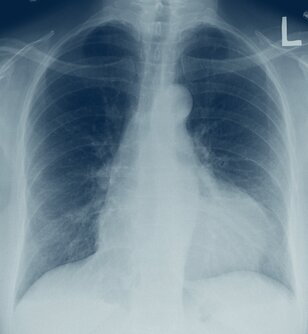

• Röntgen-Thorax: Vergrößerung des Herzschattens ohne pulmonale Stauung

Ein großer Perikarderguss hat das Herz radiologisch stark vergrößert. © wikimedia/James Heilmann.

Auch die myogene Herzdilatation kann zu einer Vergrößerung des Herzschattens im Röntgenbild führen, allerdings liegen dann gleichzeitig oft Zeichen der Lungenstauung vor, und sonographisch kann kein Erguss nachgewiesen werden.